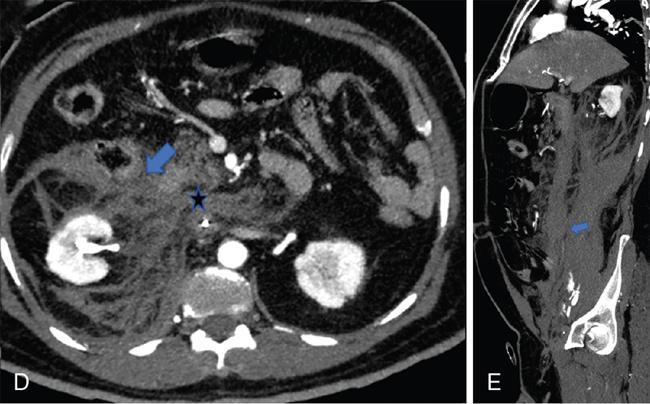

Fig. 10.17.1.9 Contrast-enhanced axial (A, B) and sagittal CT (C) sections in a case of a perinephric haematoma (asterisks in A and B). It extends into the retromesenteric and retrorenal planes by means of bridging septae which traverse the perirenal space (blue arrow in A). Inferiorly, it extends along the combined interfascial plane into the pelvis (blue arrow in C).